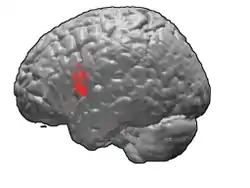

Brodmann area 44

Brodmann area 44, or BA44, is part of the frontal cortex in the human brain. Situated just anterior to premotor cortex (BA6) and on the lateral surface, inferior to BA9.

This area is also known as pars opercularis (of the inferior frontal gyrus), and it refers to a subdivision of the cytoarchitecturally defined frontal region of cerebral cortex. In the human it corresponds approximately to the opercular part of the inferior frontal gyrus. Thus, it is bounded caudally by the inferior precentral sulcus (H) and rostrally by the anterior ascending limb of lateral sulcus (H). It surrounds the diagonal sulcus (H). In the depth of the lateral sulcus it borders on the insula. Cytoarchitectonically it is bounded caudally and dorsally by the agranular frontal area 6, dorsally by the granular frontal area 9 and rostrally by the triangular part of inferior frontal gyrus (Brodmann area 45 BA 45).

Animation.

Frontal view.

Lateral view.